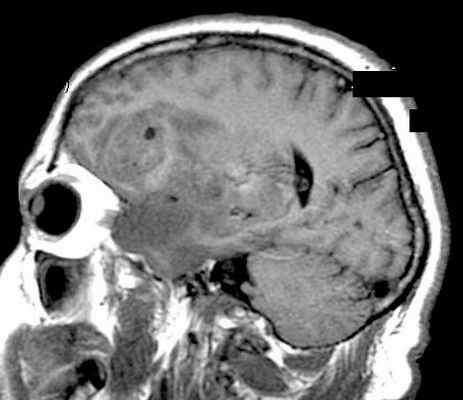

МРТ головного мозга. Астроцитома с большой реактивной кистой. Аксиальная Т2-зависимая и сагиттальная Т1-зависимая МРТ.